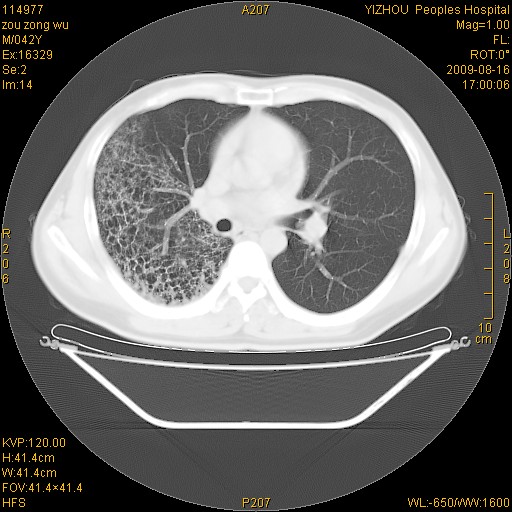

以下是引用zjzjr在2009-8-17 10:42:00的发言:[br]右侧间质性肺炎伴纤维化,右肺下叶肺囊肿伴感染(不除外外伤后引起),右肺野及胸壁软组织\\肝内见多发斑点状,中枪了吧.右侧胸膜肥厚\\粘连.